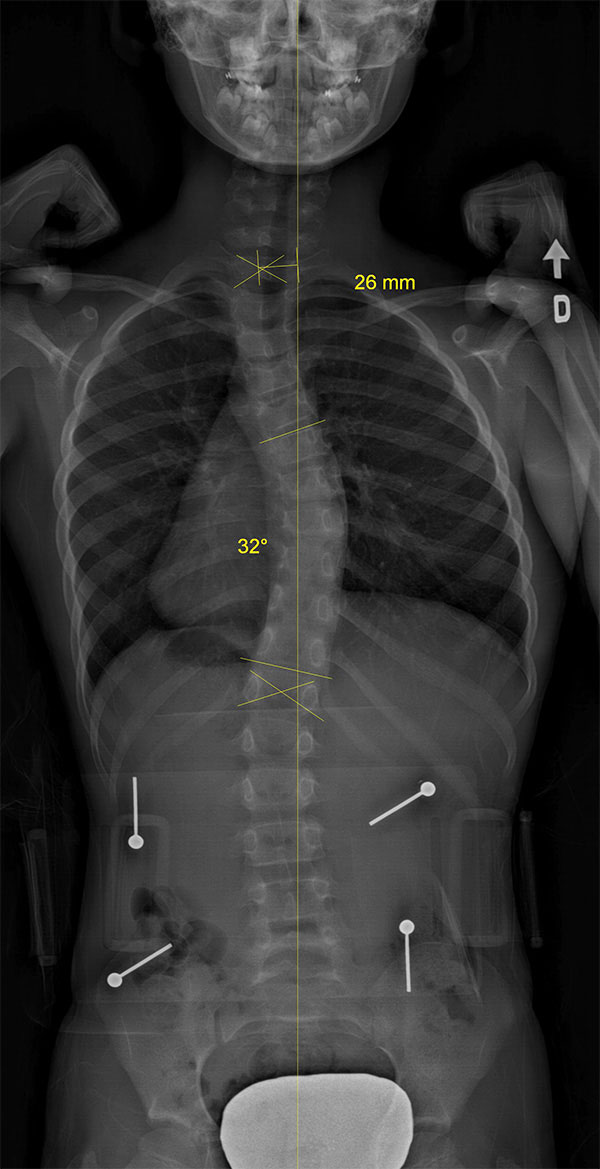

Adolescente scoliotique avant et après SpineCor®

Colonne vertébrale scoliotique d’une adolescente, avant le traitement SpineCor® et à la fin du sevrage après trois ans de port quotidien. Les radiographies démontrent une correction spectaculaire.

Colonne vertébrale de l'adolescente avant SpineCor® |

Colonne vertébrale de l'adolescente avec SpineCor® |